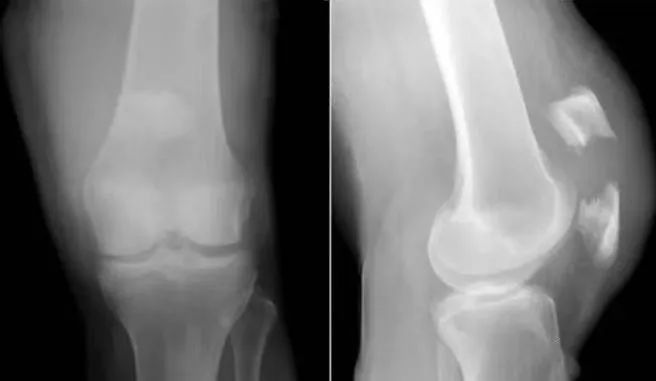

股骨髁部及髁上骨折:受伤暴力较大,压痛点在股骨髁部及髁上,可出现畸形,有骨擦音,X线摄片可鉴别。

胫骨平台骨折:压痛点在胫骨内外侧平台,髌骨前面摸不到裂隙;X线摄片可鉴别。

(6)胫骨髁骨折

股骨髁部骨折:暴力强大,压痛点在股骨髁部,X线片示股骨髁骨折。